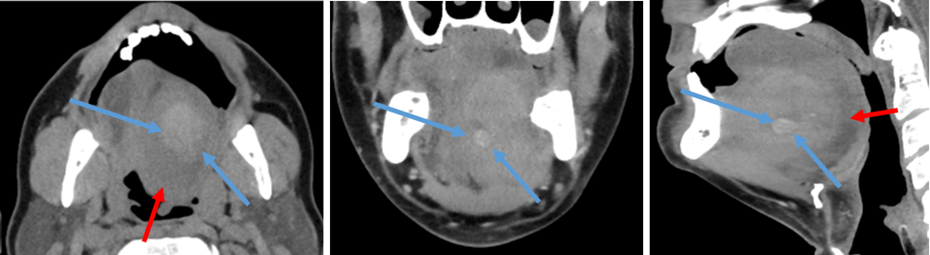

Postoperative scan, ten days after initial evacuation of the hematoma showed a progressive enlargement of the lingual artery, suggesting a traumatic lingual arterial pseudoaneurysm. Selective angiography identified active bleeding from the left lingual artery and coil embolization was performed successfully. Post-embolization angiography confirmed cessation of extravasation (Figure 3).

Figure 3: pre (A-B) -and post (C-D) endovascular coiling. Note the dimensions of the aneurysm (7.3x6.7mm) (courtesy: dr. P. Stabel, AZTurnhout).